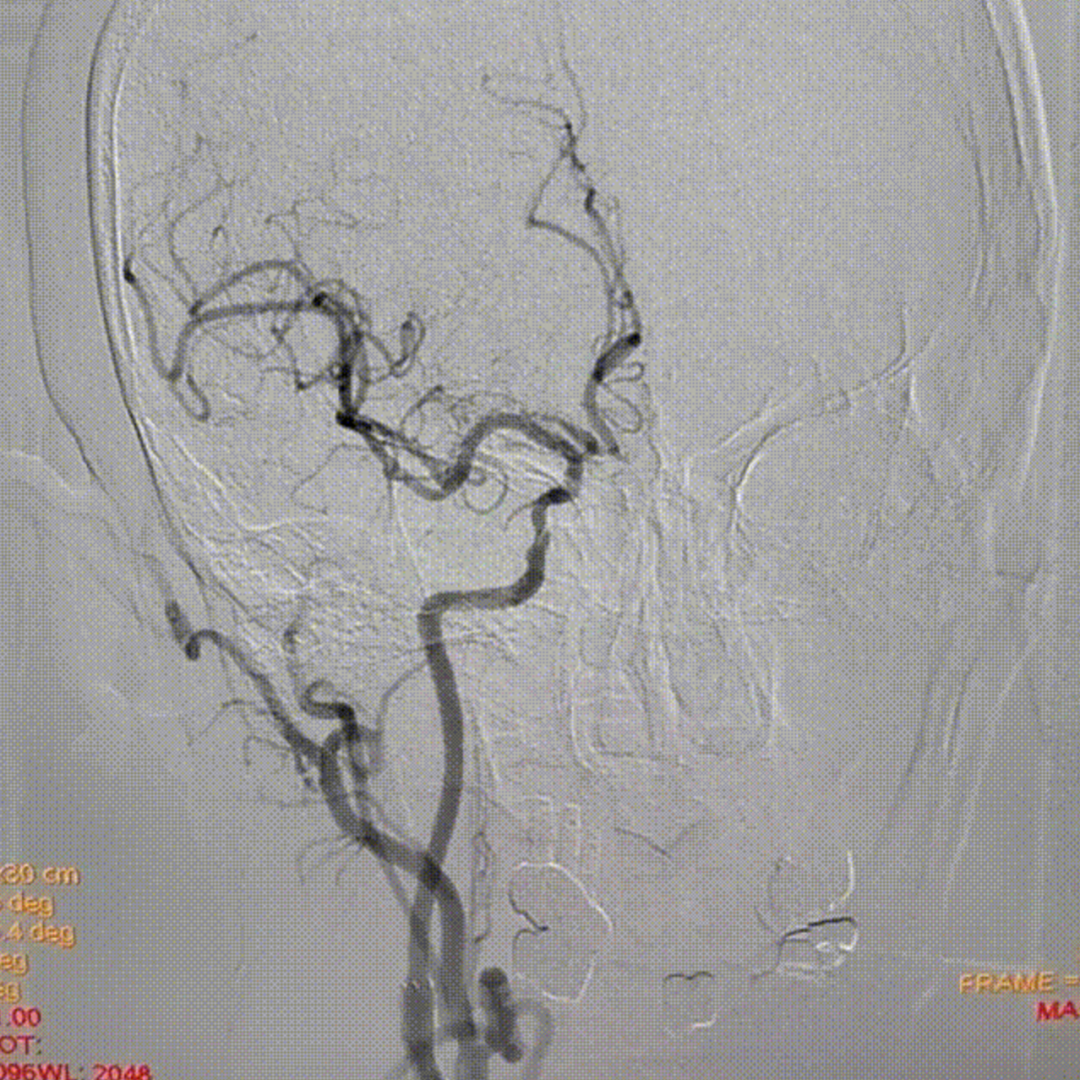

病例2:52岁男性,发作性胸痛2年,体检发现双侧颈动脉狭窄,冠脉情况严重,先行PCI,后行双侧CAS,先右后左,术后复查颈动脉支架通畅。

右侧术前

右侧术后

左侧术前

左侧术后